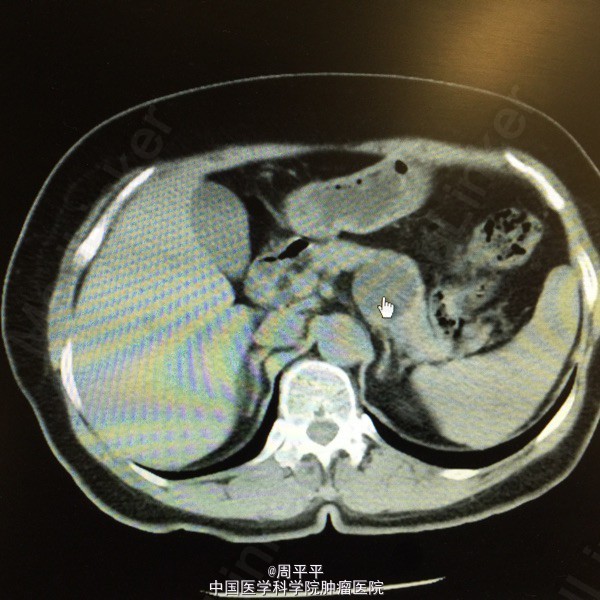

主诉:体检发现胰腺肿物18月 现病史:患者18月前因心慌不适就诊于当地医院,行腹部超声提示胰尾部囊性占位,大小约1.7×2.7cm,无腹痛、腹胀,无皮肤粘膜黄染等不适。4月前,在外院查腹部CT提示胰尾囊性肿物较前增大,约3.5×2.3cm。后于我院就诊,查血CA19-9 6.4。发病中,无腹痛、黄染等不适。体重无明显变化。 既往史:既往有频发房早,口服倍他乐克,安博诺无诉不适。

查体:全腹无压痛,未触及明显包块。 辅助检查: 腹部增强CT+三维重建:胰体部类圆形囊性密度影,大小约3.0×2.6×3.4cm,脾动、静脉受压移位。

诊断: 胰腺占位 行腹腔镜下胰体尾+脾切除。术后恢复良好。术后病理回报:胰腺粘液性囊腺瘤。

讨论:患者中老年女性,体检发现胰尾部占位,外院查腹部CT提示胰尾囊性肿物,大小约3.5×2.3cm,查血CA19-9 6.4U/ml。根据影像学检查,考虑浆液性囊腺瘤可能性大。该病为最常见的胰腺囊性肿瘤,起源于胰腺腺泡细胞,囊液清亮稀薄,富含糖原,囊壁光滑,无无恶变倾向。